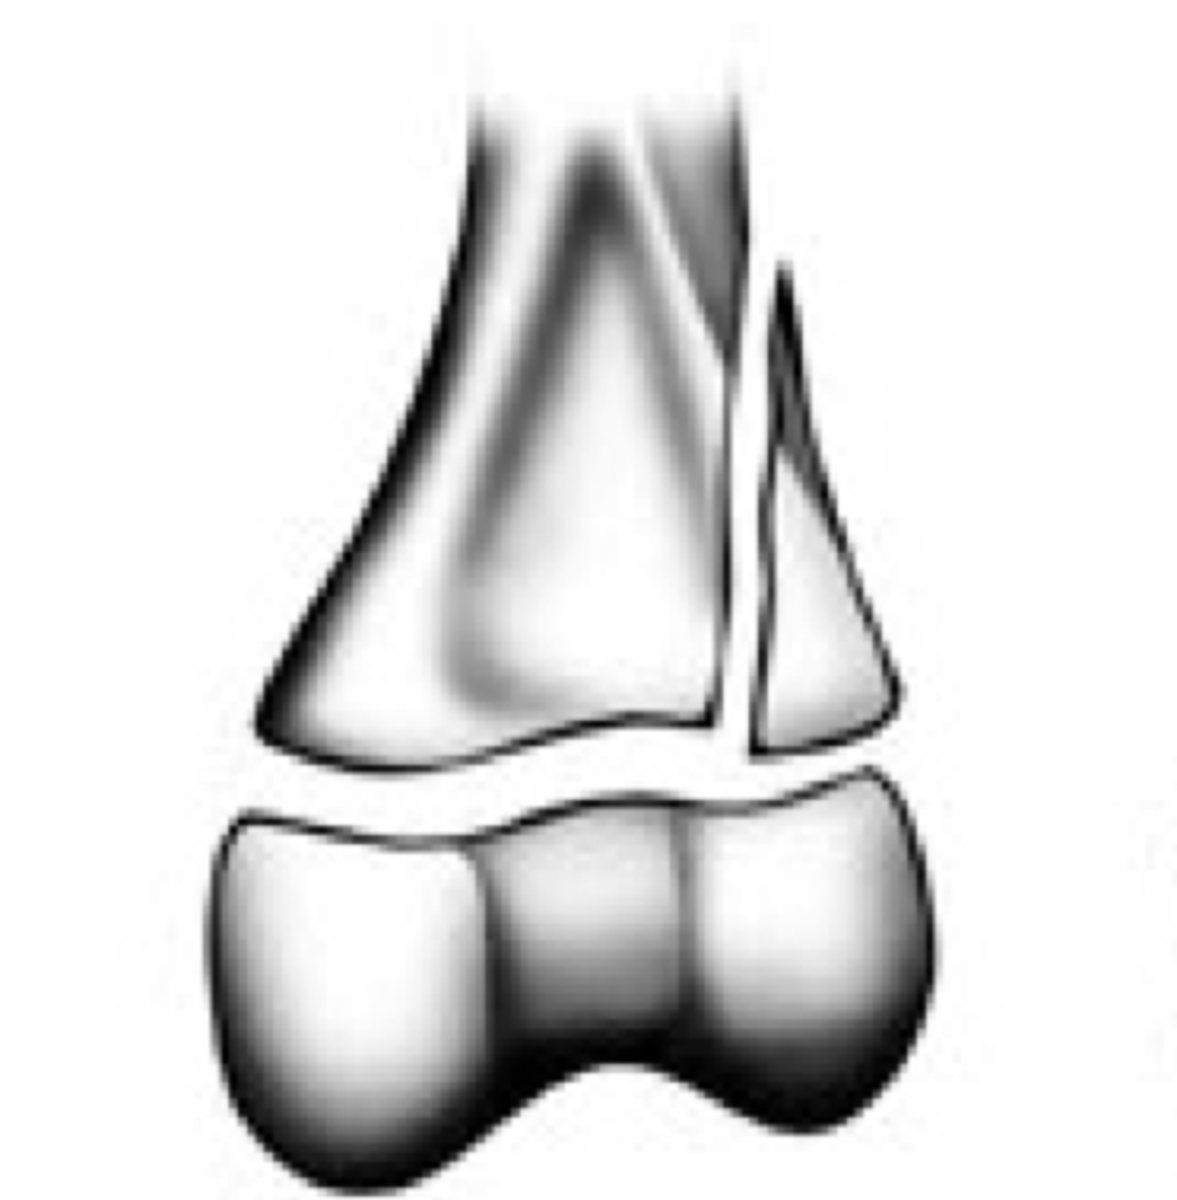

Grade the Salter-Harris fracture?

1 - straight through the physis

Straight across

5 - compression upon physis

ERasure of the growth plate or compression